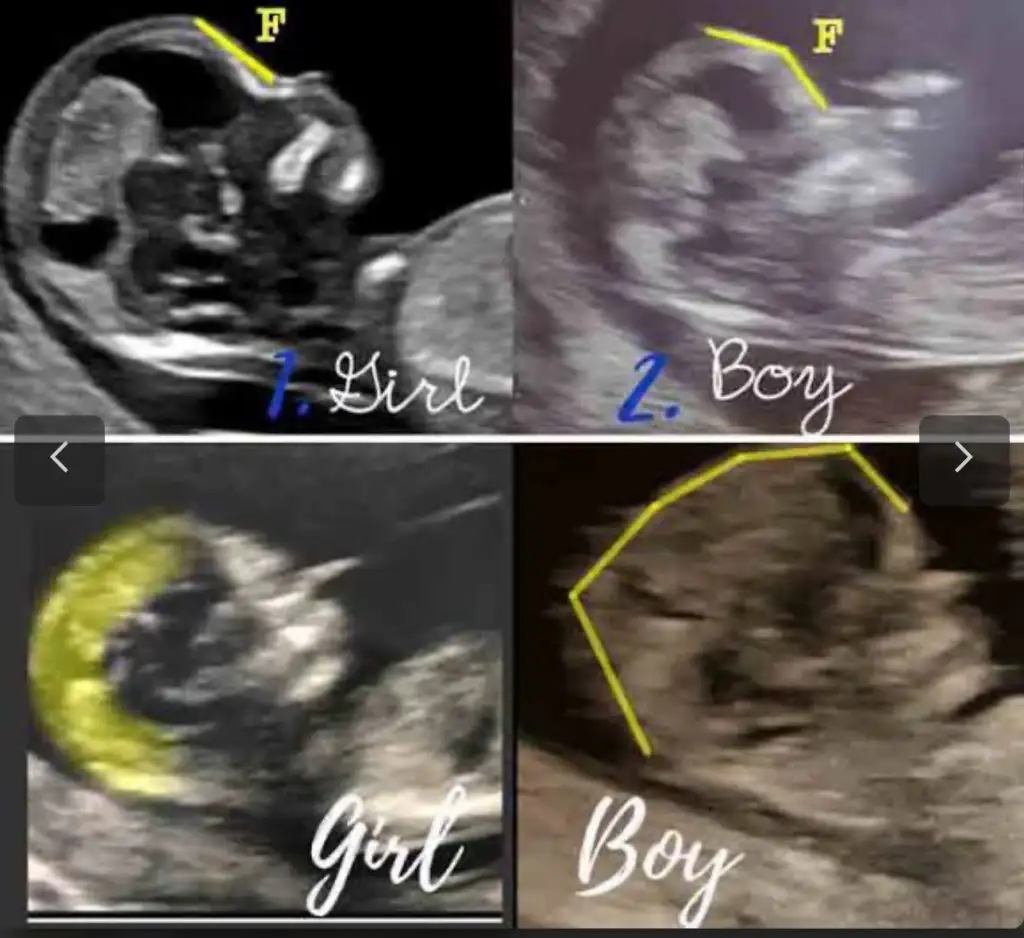

Canım yuvarlak ve daha biçimli duran kafa erkek , sivri alın daha köşeli kafa kız diyorlar ama mesela bir arkadaşıma kız dedim kafadan erkek çıktı, buda tutmuyor yani😅

Ben tam tersi diye biliyorum. Köşeli erkek, yuvarlak kız.